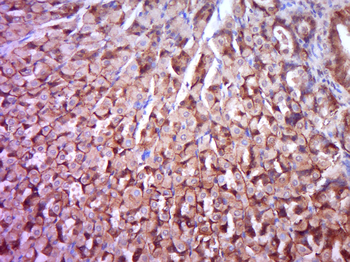

Tissue/Cell: mouse stomach tissue, 4% Fixative-fixed and paraffin-embedded, Antigen retrieval: citrate buffer (0.01M, pH6.0), Boiling bathing for 15 min, Block endogenous peroxidase by 3% Hydrogen peroxide for 30 min, Blocking buffer (normal goat serum) at 37°C for 20 min, Incubation: Anti-phospho-PKC delta Polyclonal Antibody, Unconjugated (orb6753) 1:200, overnight at 4°C, followed by conjugation to the secondary antibody and DAB staining.